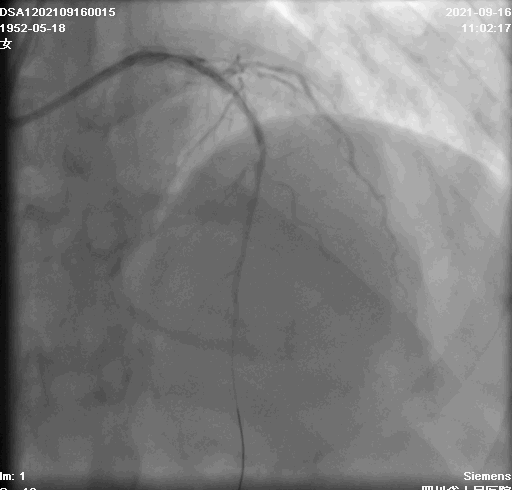

现病史:半月前因胸痛伴上腹疼痛在四川省人民医院CCU住院治疗,诊断为“急性下壁、正后壁ST短抬高型心肌梗死,冠心病,2型糖尿病”,于8月30日行冠脉造影术见前降支及右冠狭窄明显,并行右冠状动脉支架置入两枚。当时建议行前降支PCI,患者拒绝,随后病情好转出院。术后患者未再发胸痛,偶有心悸不适,晚上7-8点明显,持续半小时可自行缓解。后于9月15日就诊入院。

冠状动脉造影+准分子激光冠脉斑块消蚀术(ELCA)+光学相干断层成像(OCT)+支架植入术。

术中影像

激光消蚀后前降支病变处最大管腔>6mm²,未见血栓及夹层,支架植入后复查CTO支架贴壁良好,扩张充分,未见血肿及夹层,手术效果良好。